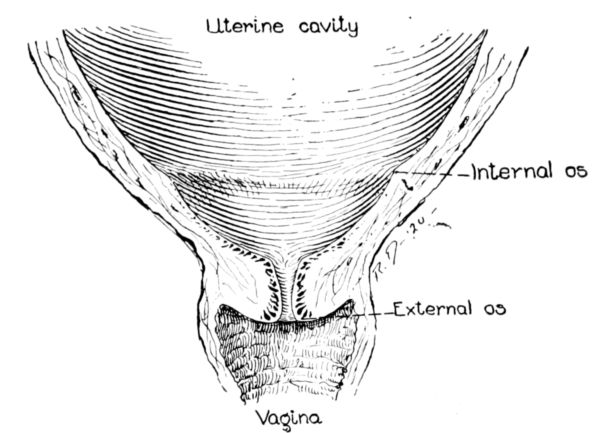

| xxi63, 64, 65, 66. | Diagrams showing stages of dilatation and obliteration of cervix | 234 |

The uterus as a whole is comprised of three parts: the fundus, that firm, rounded, head-like part above; the body, or middle portion, and the cervix, or neck, below. It is in the body and cervix that we find the long, narrow uterine cavity, divided by a constriction into two parts. The cavity of the body is little more than a vertical slit, being so flattened from before backward 33that the anterior and posterior surfaces are nearly if not quite in apposition. It is somewhat triangular in shape with an opening at each angle. (Fig. 11.) The lower of these openings leads into the cavity of the cervix through a constriction termed the internal os, while at the cornua, or two upper angles, are the openings into the Fallopian tubes.

The cavity of the cervix is spindle-shaped, being expanded between its two constricted openings, the internal os above and the external os below, which opens into the vagina. The external os in the virgin is a small round hole but has a ragged outline in women who have borne children.